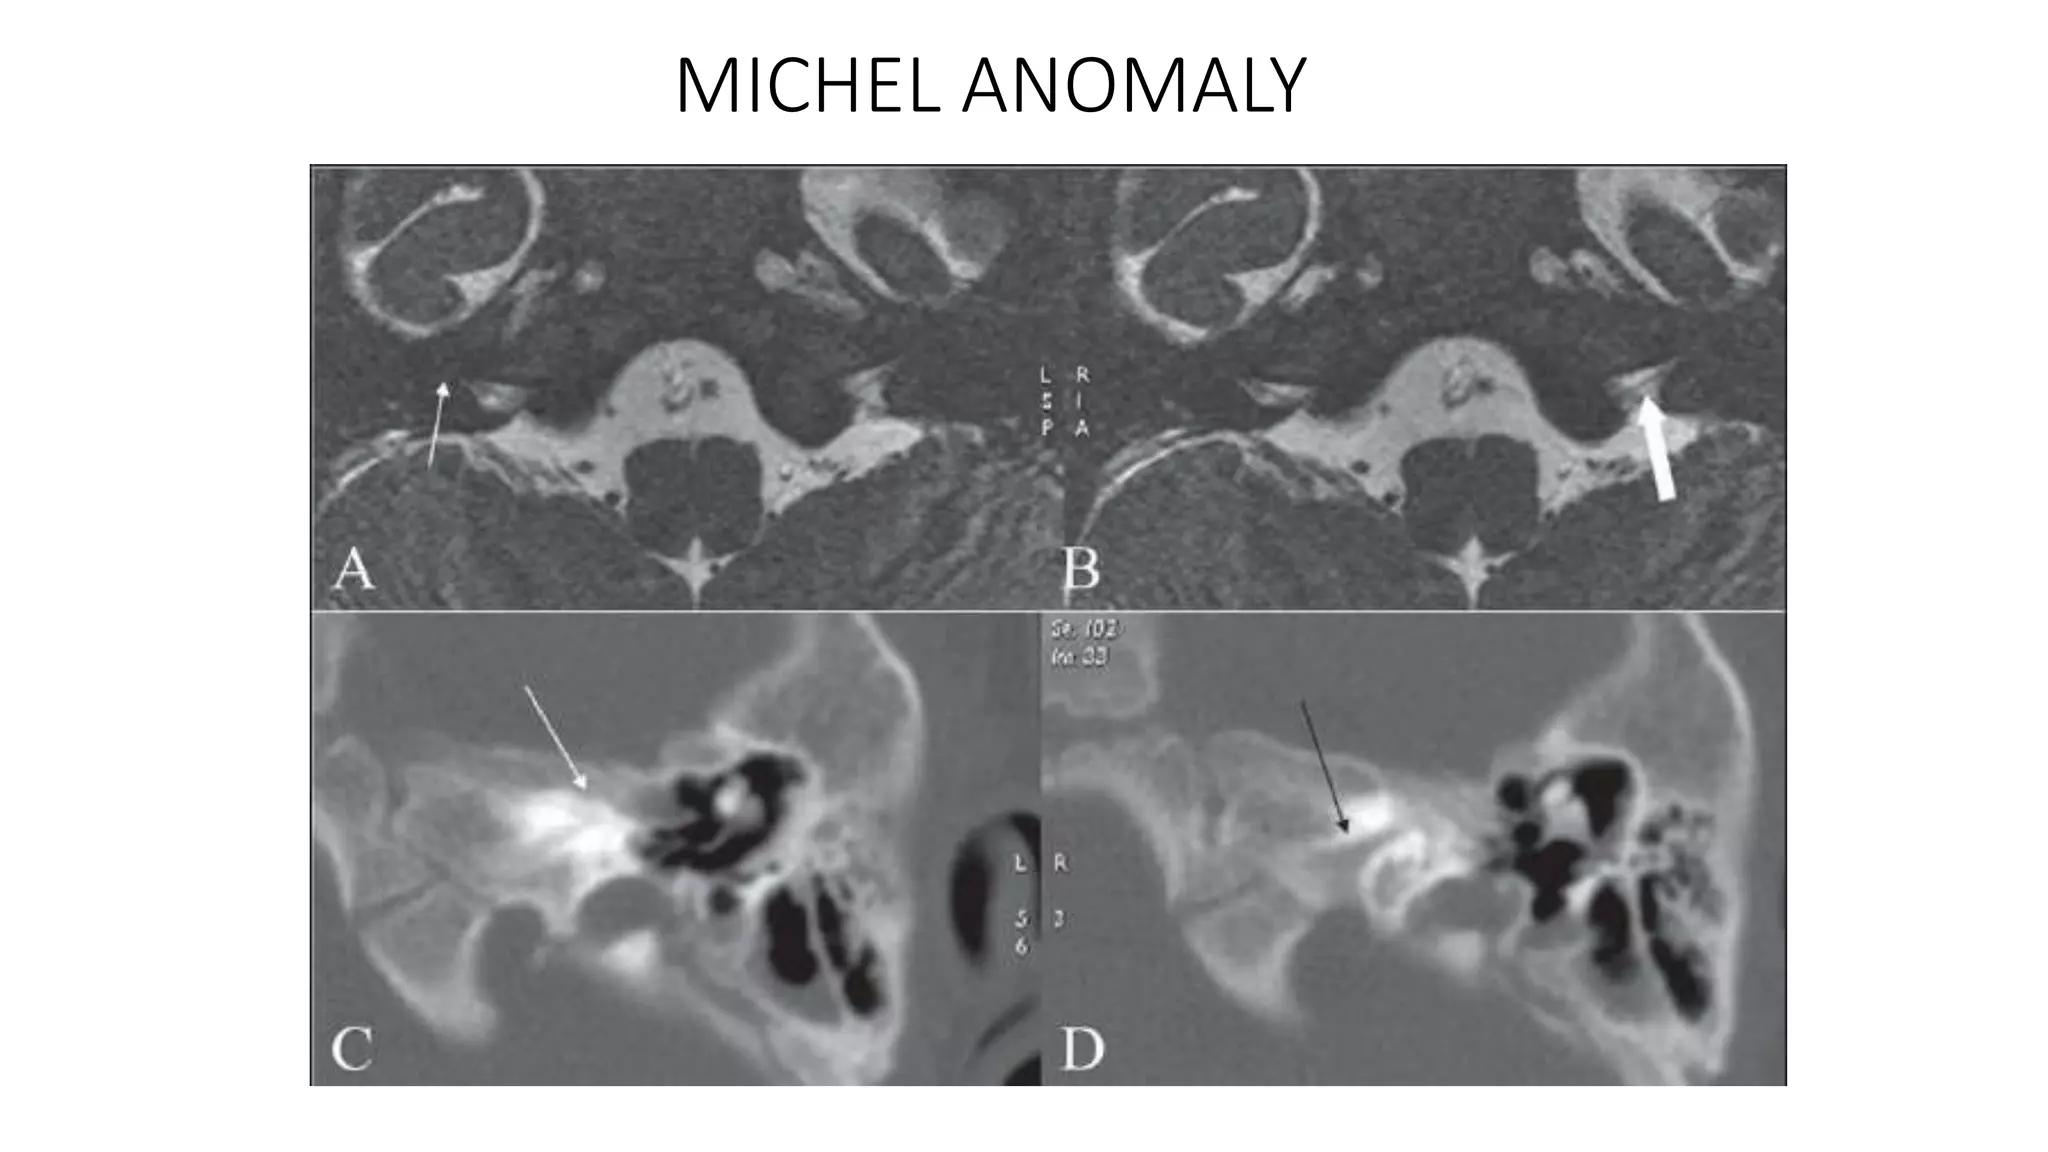

MICHEL ANOMALY

complete absence of inner ear structures

Michel’s deformity

Axial 3D FIESTA showing Michel's deformity on right side (red arrow) in the

form of complete absence of inner ear structures.

MICHEL ANOMALY complete absenceof inner ear structures

Michel’s deformity Axial 3DFIESTA showing Michel's deformity on right side (red arrow) in the form of complete absence of inner ear structures.